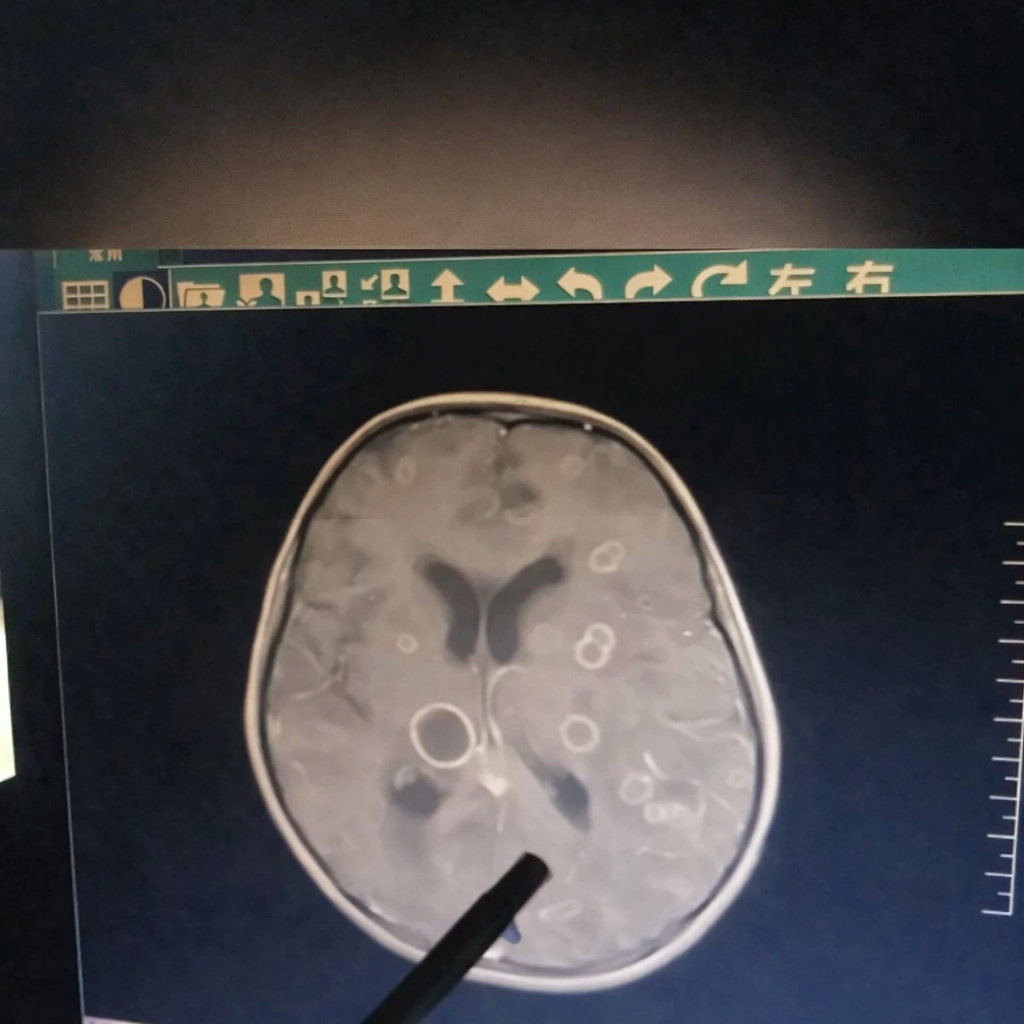

Kết quả kiểm tra khiến các bác sĩ không khỏi bàng hoàng: Trong não của đứa trẻ xuất hiện hơn chục ổ tổn thương lớn nhỏ, giống như bị “gặm nhấm” từng mảng.

Mới đây, một bé gái 6 tuổi ở Trung Quốc bị sốt liên tục suốt 17 ngày, dần rơi vào tình trạng lơ mơ, rối loạn ý thức và được chuyển gấp tới Bệnh viện trực thuộc Đại học Trịnh Châu (Trung Quốc). Kết quả kiểm tra khiến các bác sĩ không khỏi bàng hoàng: trong não của đứa trẻ xuất hiện hơn chục ổ tổn thương lớn nhỏ, giống như bị “gặm nhấm” từng mảng.

Bác sĩ cho biết, nếu đến muộn thêm vài ngày, tổn thương có thể lan rộng đến mức đe dọa trực tiếp tính mạng.